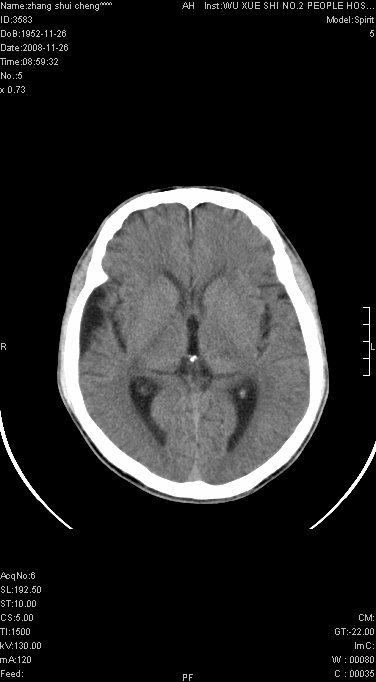

男.68.肢体无力多年

请问是蛛网膜囊肿.还是软化灶.原有中风

脑外性,蛛网膜囊肿

支持右侧颞区蛛网膜囊肿。

蛛网膜囊肿,软化灶周围脑沟应该受牵拉,扩大